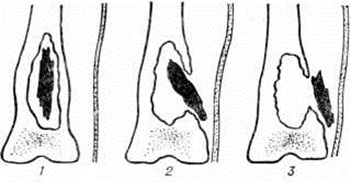

Рис. 3. Макропрепарат метафиза бедренной кости при гематогенном остеомиелите: 1 — внутрикостные гнойники с секвестрами губчатого вещества; 2 — субпериостальный гнойник.